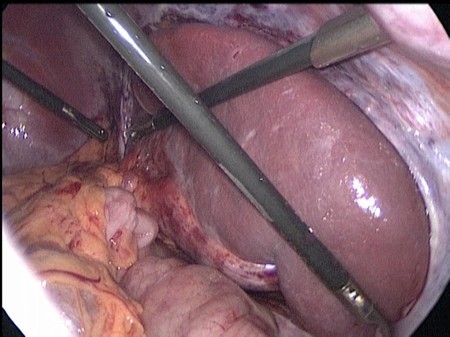

Рис 1. Интраоперационное фото. Связочный аппарат селезенки отсутствует. Имеется перекрут селезенки на 180 градусов, расширение и извитость селезеночной вены.

Произведена деторзия селезенки, последняя легко смещается по брюшной полости. Продольно рассечен листок брюшины по левому боковому каналу, листки брюшины мобилизованы. В созданный в забрюшинном пространстве карман уложена селезенка (Рис. 2).